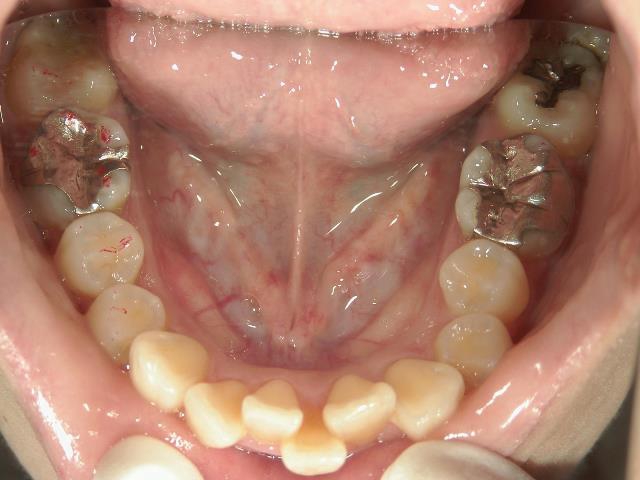

矯正歯科(全顎ワイヤー矯正)治療後

矯正歯科 治療後